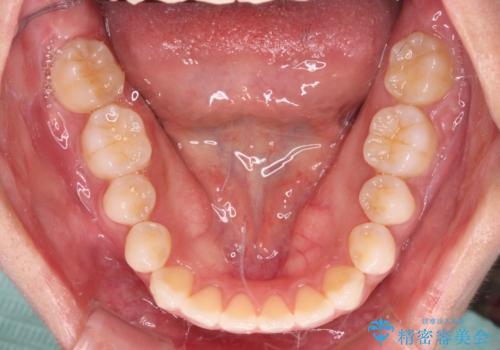

- 前に出ている上顎前歯が気になるとのことで来院された患者様です。

インビザラインを用い、IPR(歯と歯の間を削る)と歯列全体を後方に移動させることで、可能な限り前歯の突出感を改善することとしました。

元々の歯列も整っており、横顔の印象の出っ歯ではなかったため、仕上がりに満足できない可能性があると心配しておりましたが、口が閉じやすくなり、患者様には大変満足していただきました。